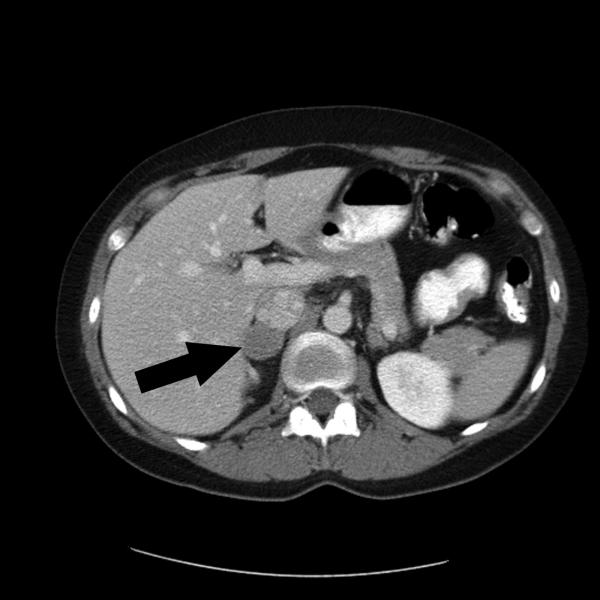

This image is a SPECT image that shows a rare adrenaline-producing tumor called adrenal pheochromocytoma.